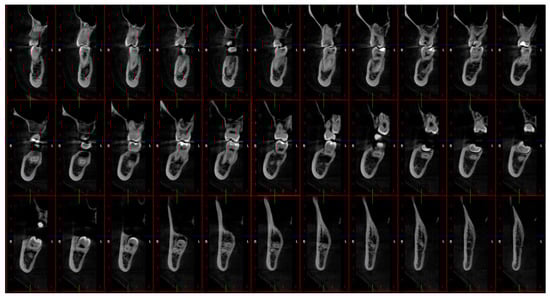

Romexis 6.2 software (Planmeca oy, Helsinki, Finland) was used to process the scans and generate 33 cross-sectional images (Figure 1) from each scan for further evaluation. This software was used as it facilitates the export of the segmented structure as a Standard Triangle Language (STL) file. Two independent investigators (an oral and maxillofacial radiologist with over ten years of experience and a trainee in oral and maxillofacial radiology with three years of experience) evaluated the images on an NEC MultiSync EA245WMi-2 display screen (Sharp NEC DisplaySolutions, Tokyo, Japan) under optimal ambient lighting conditions. The evaluation was repeated twice, with a 10-day interval. The investigators rated the visibility of the IAC based on a 3-score classification (good, average, and poor), as shown in Table 2. The Brightness value in Romexis 6.2 software (Planmeca oy, Helsinki, Finland) was fixed to 1808 by default.

Figure 1.

Snapshot of 33 cross-sectional images on Romexis 6.2 software (Planmeca oy, Helsinki, Finland): 0.25 mm thickness, sharpness, and contrast at zero.